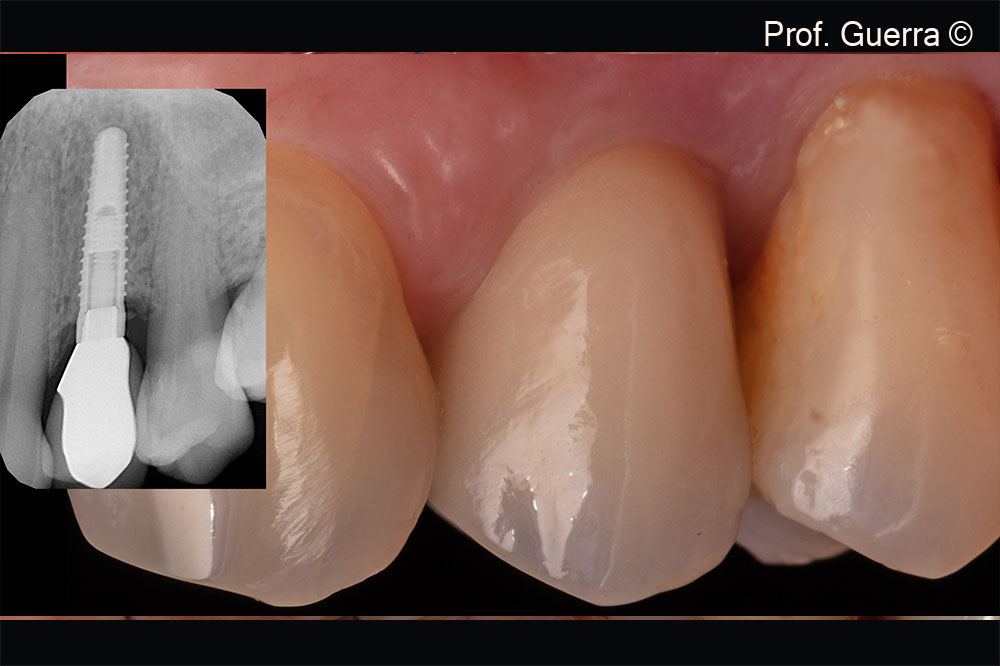

Treatment of a bone dehiscence in the upper jaw

Prof. Fernando Guerra, Dr. Rui Falacho

3 years folllow-up